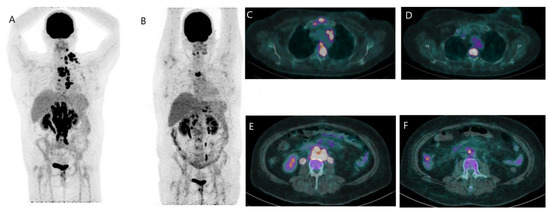

- Kömek, H.; Can, C.; Güzel, Y.; Oruç, Z.; Gündoğan, C.; Yildirim, Ö.A.; Kaplan, İ.; Erdur, E.; Yıldırım, M.S.; Çakabay, B. 68Ga-FAPI-04 PET/CT, a new step in breast cancer imaging: A comparative pilot study with the 18F-FDG PET/CT. Ann. Nucl. Med. 2021, 35, 744–752. [Google Scholar] [CrossRef]